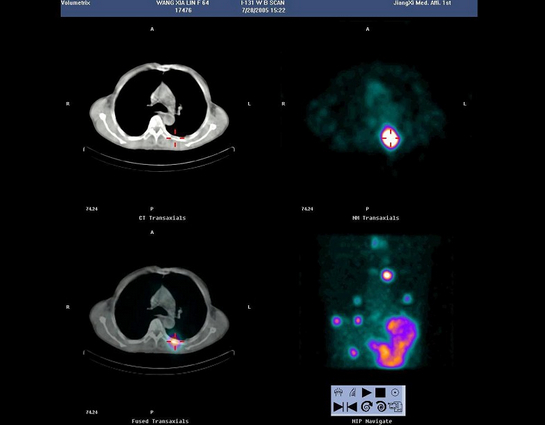

15、多项选择题

63岁男性,甲状腺滤泡状癌术后3年,行I全身显像及SPECT/CT图像融合如图,正确的诊断是()